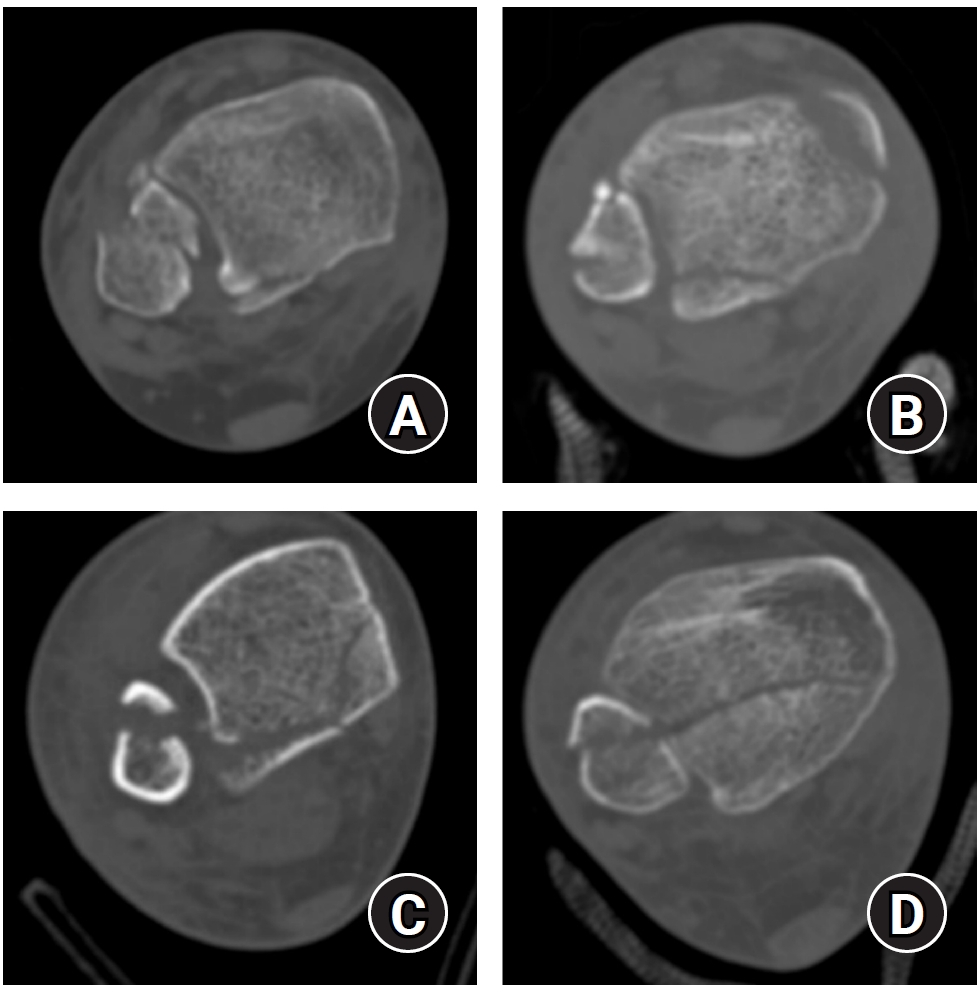

Posterior malleolar fracture morphology was classified according to the Haraguchi and Bartonicek systems (Figs. 2, 3) [19,20]. The peak height of the posterior malleolar fracture was measured as the vertical distance from the highest point of the distal tibial articular surface to the fracture apex in the sagittal plane (Fig. 4A). The articular surface area of the posterior malleolar fragment was calculated using the region of interest tool in a picture archiving and communication system (Maroview 5.4; INFINITT Healthcare) (Fig. 4B). All quantitative radiographic measurements were performed by two orthopedic surgeons; mean values were used. For categorical variables, disagreements were resolved by consensus.

Fig. 2.

Haraguchi classification of posterior malleolar fractures. (A) Type I: posterolateral-oblique type. (B) Type II: medial-extension type. (C) Type III: small-shell type.

jmt-2025-00234f2.jpg

Fig. 3.

Bartonicek classification of posterior malleolar fractures. (A) Type 1: extraincisural fragment with an intact fibular notch. (B) Type 2: posterolateral fragment extending into the fibular notch. (C) Type 3: posteromedial two-part fragment involving the medial malleolus. (D) Type 4: large posterolateral triangular fragment.

jmt-2025-00234f3.jpg